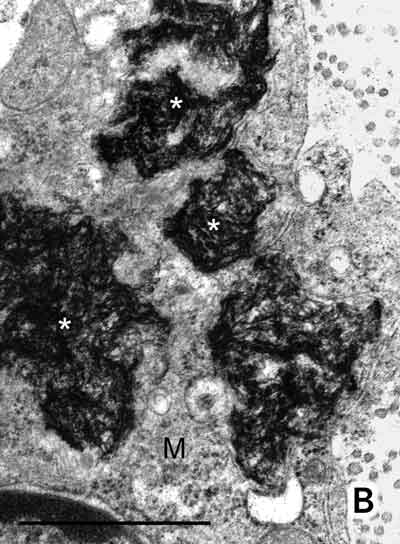

The interstitial connective tissue of the deltoid muscle contained a dense infiltrate of large macrophages (Figure A). Electron microscopy showed spiculated structures within these macrophages (Figure B). When an electron beam hits a sample it releases x-rays of wavelength specific to the elements in the sample. Using this principle, an EDAX x-ray detector revealed an aluminium peak (Kα, 1.48 keV) from the aggregates.

A: Deltoid muscle biopsy. Densely packed macrophages with abundant cytoplasm (arrowhead) were seen between muscle fibres (M), together with a few peripheral lymphocytes (thin arrow). No muscle fibre necrosis, regeneration, multinucleate giant cells, Michaelis–Guttmann bodies (found in malakoplakia) or granulomas were present. The macrophages stained positively with acid phosphatase and CD68. The lymphoid population showed a mixture of T and B lymphocytes. Stains for acid-fast bacilli were negative. (Haematoxylin and eosin. Bar = 50 m.) B: Electron micrograph showing electron-dense, randomly orientated, fine spiculated structures (asterisks) within a macrophage (M) (200 nm resin sections on nickel grids examined in a Philips CM120 electron microscope. Osmium and uranyl acetate. Bar = 1 µm.)